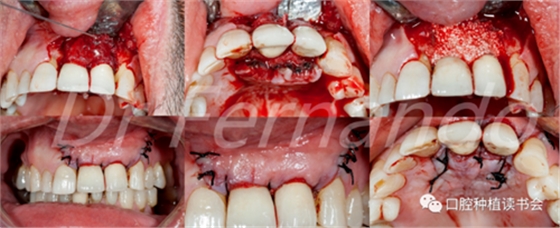

在治療種植體周圍炎方面,唯一有效的治療方法是進行外科手術(圖4 )。然而,手術治療只是部分有效;Leonhardt等人 描述在5年的時間里,超過一半的種植體周圍炎使用手術和抗菌治療是有效的。Heitz-Mayfield等 也證明,在短期(1年)內(nèi),用外科翻瓣加抗菌治療能夠有效地阻止90%的種植體周圍炎的發(fā)展;但在這些病例中,仍有50%的患者有探診出血。

圖4 前牙美學區(qū)種植體周圍炎采用手術&骨再生治療

盡管手術治療似乎能改善結果;但只有將手術治療和骨再生相結合才能獲得更高的成功率。Schwarz等人發(fā)現(xiàn)這種再生手術治療有2年以上的滿意效果,能使種植體周圍的骨吸收停止,探診出血率由80%降至34%(圖5 )。

圖5通過手術治療,種植體周圍獲得骨再生,術后2年效果穩(wěn)定(圖2、圖4相同病例)